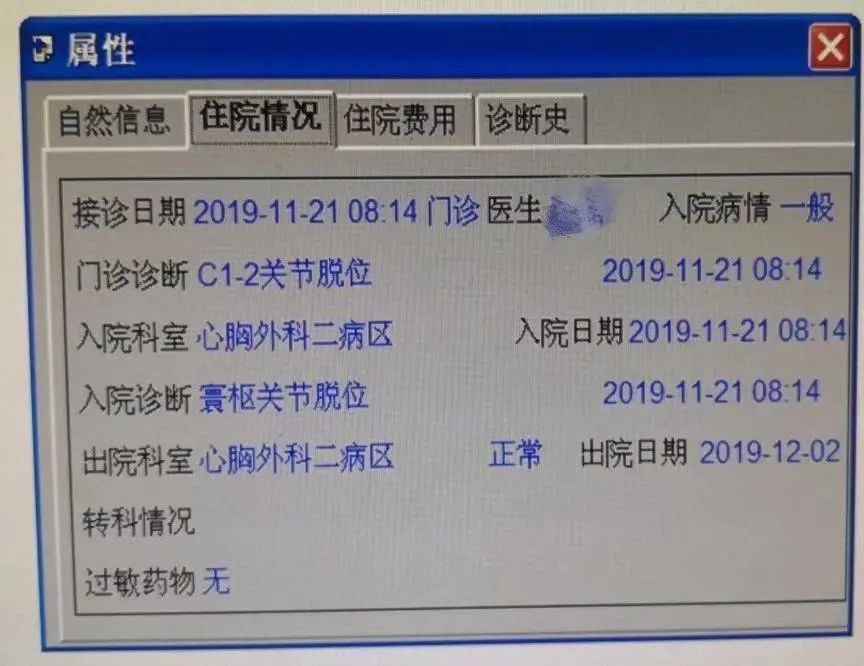

51岁的张阿姨患类风湿性关节炎20多年。2019年11月,女儿带她去了家门口的足疗按摩店。除了捏脚,还做了颈肩背部按摩。

(不当按摩动作模拟,请勿模仿。图片来源:自己拍的)张阿姨也没能“逃”过这组“程序化”的动作。

据她回忆,当时她就感觉到,脖子深部有一种“错动”的感觉,难以用语言描述。

回家后,她慢慢地出现了呼吸困难、四肢无力等症状,随后来到医院就诊。

我让她去拍了个片子,诊断为寰枢椎脱位,脊髓损伤(说明:第1、2节颈椎分别称寰椎、枢椎)。 (作者供图)

(作者供图)后来,张阿姨住了院,并做了手术。术后恢复到生活能自理,前后花了半年时间和十几万元。真是花了钱,还受罪!